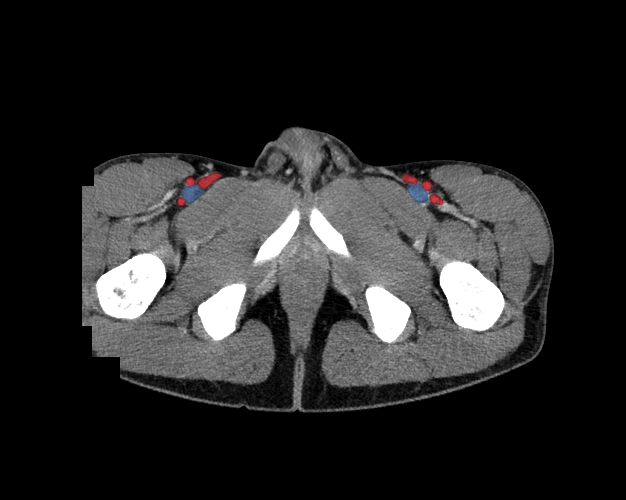

Pelvis

Covers pelvic MRI anatomy.